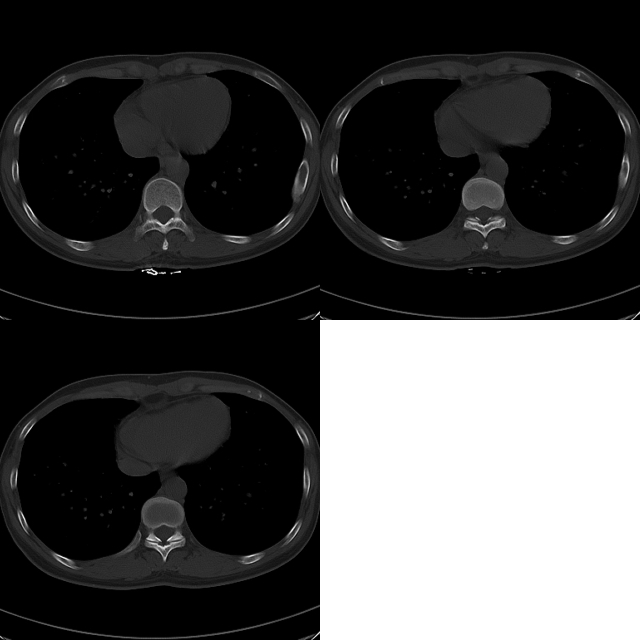

标题: CT19623:F40y,肋骨改变。

40岁女性,双侧胸部疼痛,以左侧为明显1+年。余无明显异常。

骨纤维异常增殖症。

考虑左侧肋骨骨纤维异常增殖症。

左侧肋骨单发膨胀性病变,皮质连续,病史较长,首先考虑良性病变:骨纤可能性大。